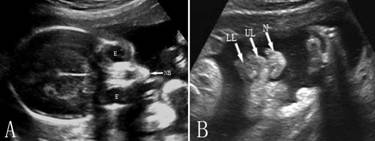

在横切面上,将探头从胎儿头颅平行向下扫查,可依次显示出胎儿双侧眶腔及眼内结构(E)、鼻骨(NB)、鼻尖(N)、左右鼻孔、上唇(UL)、上牙槽突、舌、咽、软腭、下牙槽突、下颌等(图2)。

图2 胎儿面部横断面(A)及面部冠状面(B)声像图

由于面部结构细小、复杂,显示时机、技巧、胎儿的体位、适量的羊水衬托和正确的辨认非常重要。胎儿仰卧、面部有适量的羊水状况下有利于面部的显示。鼻子和唇部的显示一般在18孕周~22孕周、面部冠状面和横断面上完成,检查过程中不断地微调探头显示平面,在理想的状态下可以显示唇线、人中、双侧鼻孔等,对辨认有无唇裂有重要的意义(图8-2B);显示上述冠状面后向后移动平面可以显示口腔和鼻腔回声及其之间的上颚,对辨认腭裂有一定的价值;但除非合并唇裂,在整个妊娠期单纯显示腭裂是非常困难的,显示率不超过1.4%。

眶腔水平的横断面可以显示典型的胎儿眶腔及眼球的回声。眶腔的内经(OD)、眶距(BOD)及眶腔内缘距离(IOD)是常用的测量指标,其中眶距是双侧眶腔外缘的距离(OOD),可以作为孕龄预测依据。眶腔及眶距的大小除与胎儿孕龄及胎儿结构有关外,也可能与染色体异常有关。衡量IOD的一个简单的办法是OOD = OD × 3。眶腔内可以显示眼球、玻璃体和晶体回声(图2A)。